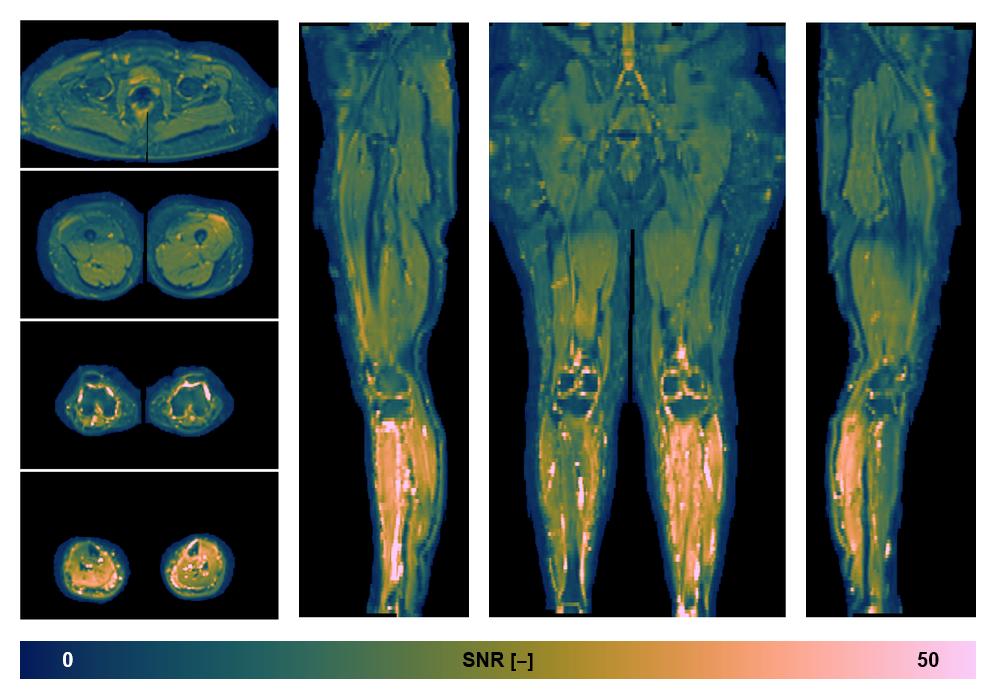

• SNR distribution

The SNR distribution of the dixon data.

• SNR of the unweighted image

SNR distribution of the unweighted diffusion data.